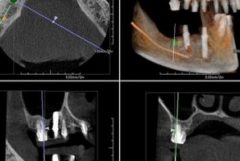

N・Sさんの右上のインプラント治療がアバットメントのスキャニングを迎えました。

インプラント埋入オペ時の記事はこちらです。

左上に2本のインプラントの埋入オペをしました。2015.10.09

インプラント埋入オペから7日後の記事はこちらです。